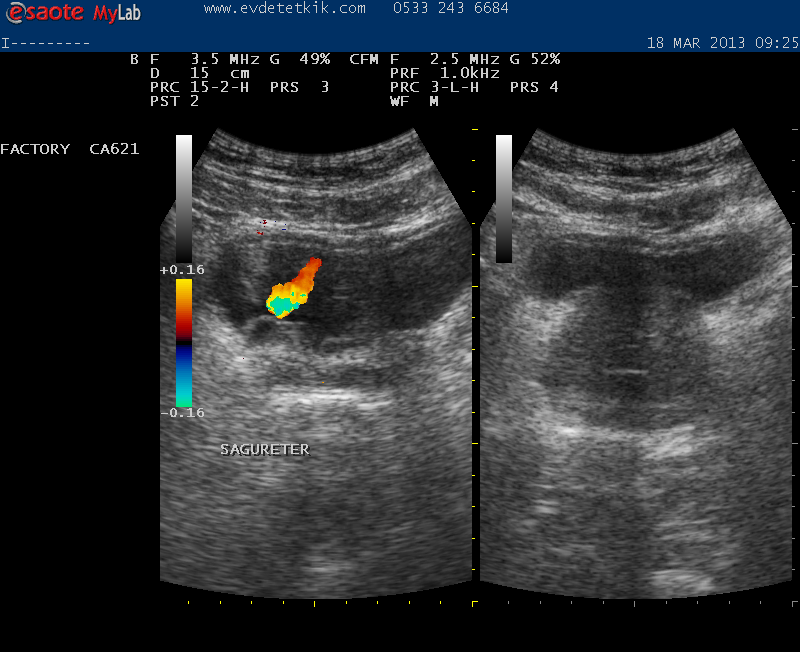

Hizmetimizden görüntüler